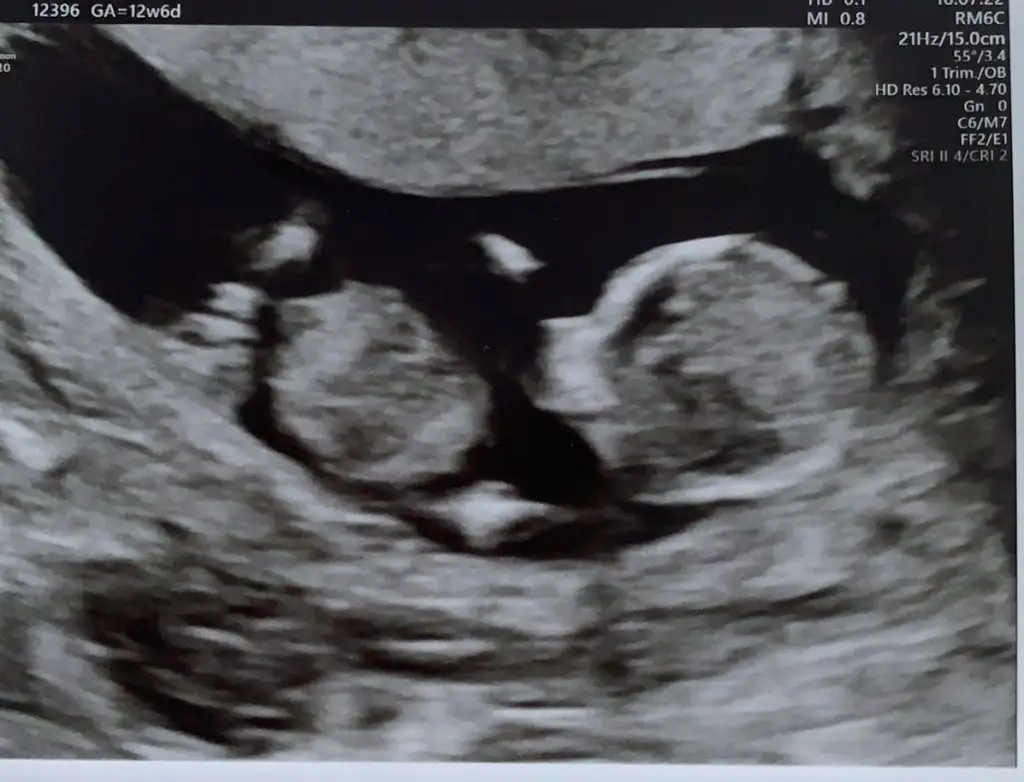

USG net değil ama nubu dik görünüyorSimdi 17 haftaligiz. Bu resimlerdede 12 haftaydi

Çok büyük gelmedi bana emin olamadım popoyada paralel değil acısı hafif dik geldi başka USG varsa teyit etmek isterimAttım tekrar bundan baslada yok 12+3

Başka yok sadece bu var tahmini hangiisnden yana kullanmak istersinÇok büyük gelmedi bana emin olamadım popoyada paralel değil acısı hafif dik geldi başka USG varsa teyit etmek isterimEki Görüntüle 2751139

Açısı dik değilÖnce kıza benzettim demiştinizbilemiyorum ama bunu dik görünüyor gibi dikkatlice bakarsanız görürsünüz Eki Görüntüle 2751645